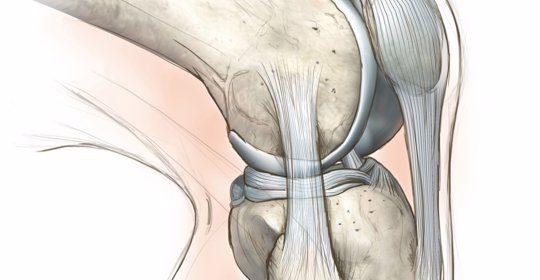

腱反射亢進:神經系統的紊亂,症狀辨析及科學疏導方法

腱反射消失:神經失調的跡象,症狀及科學調理方法詳解

脊神經壓迫:背部的煎熬,症狀與科學疏導方法詳解